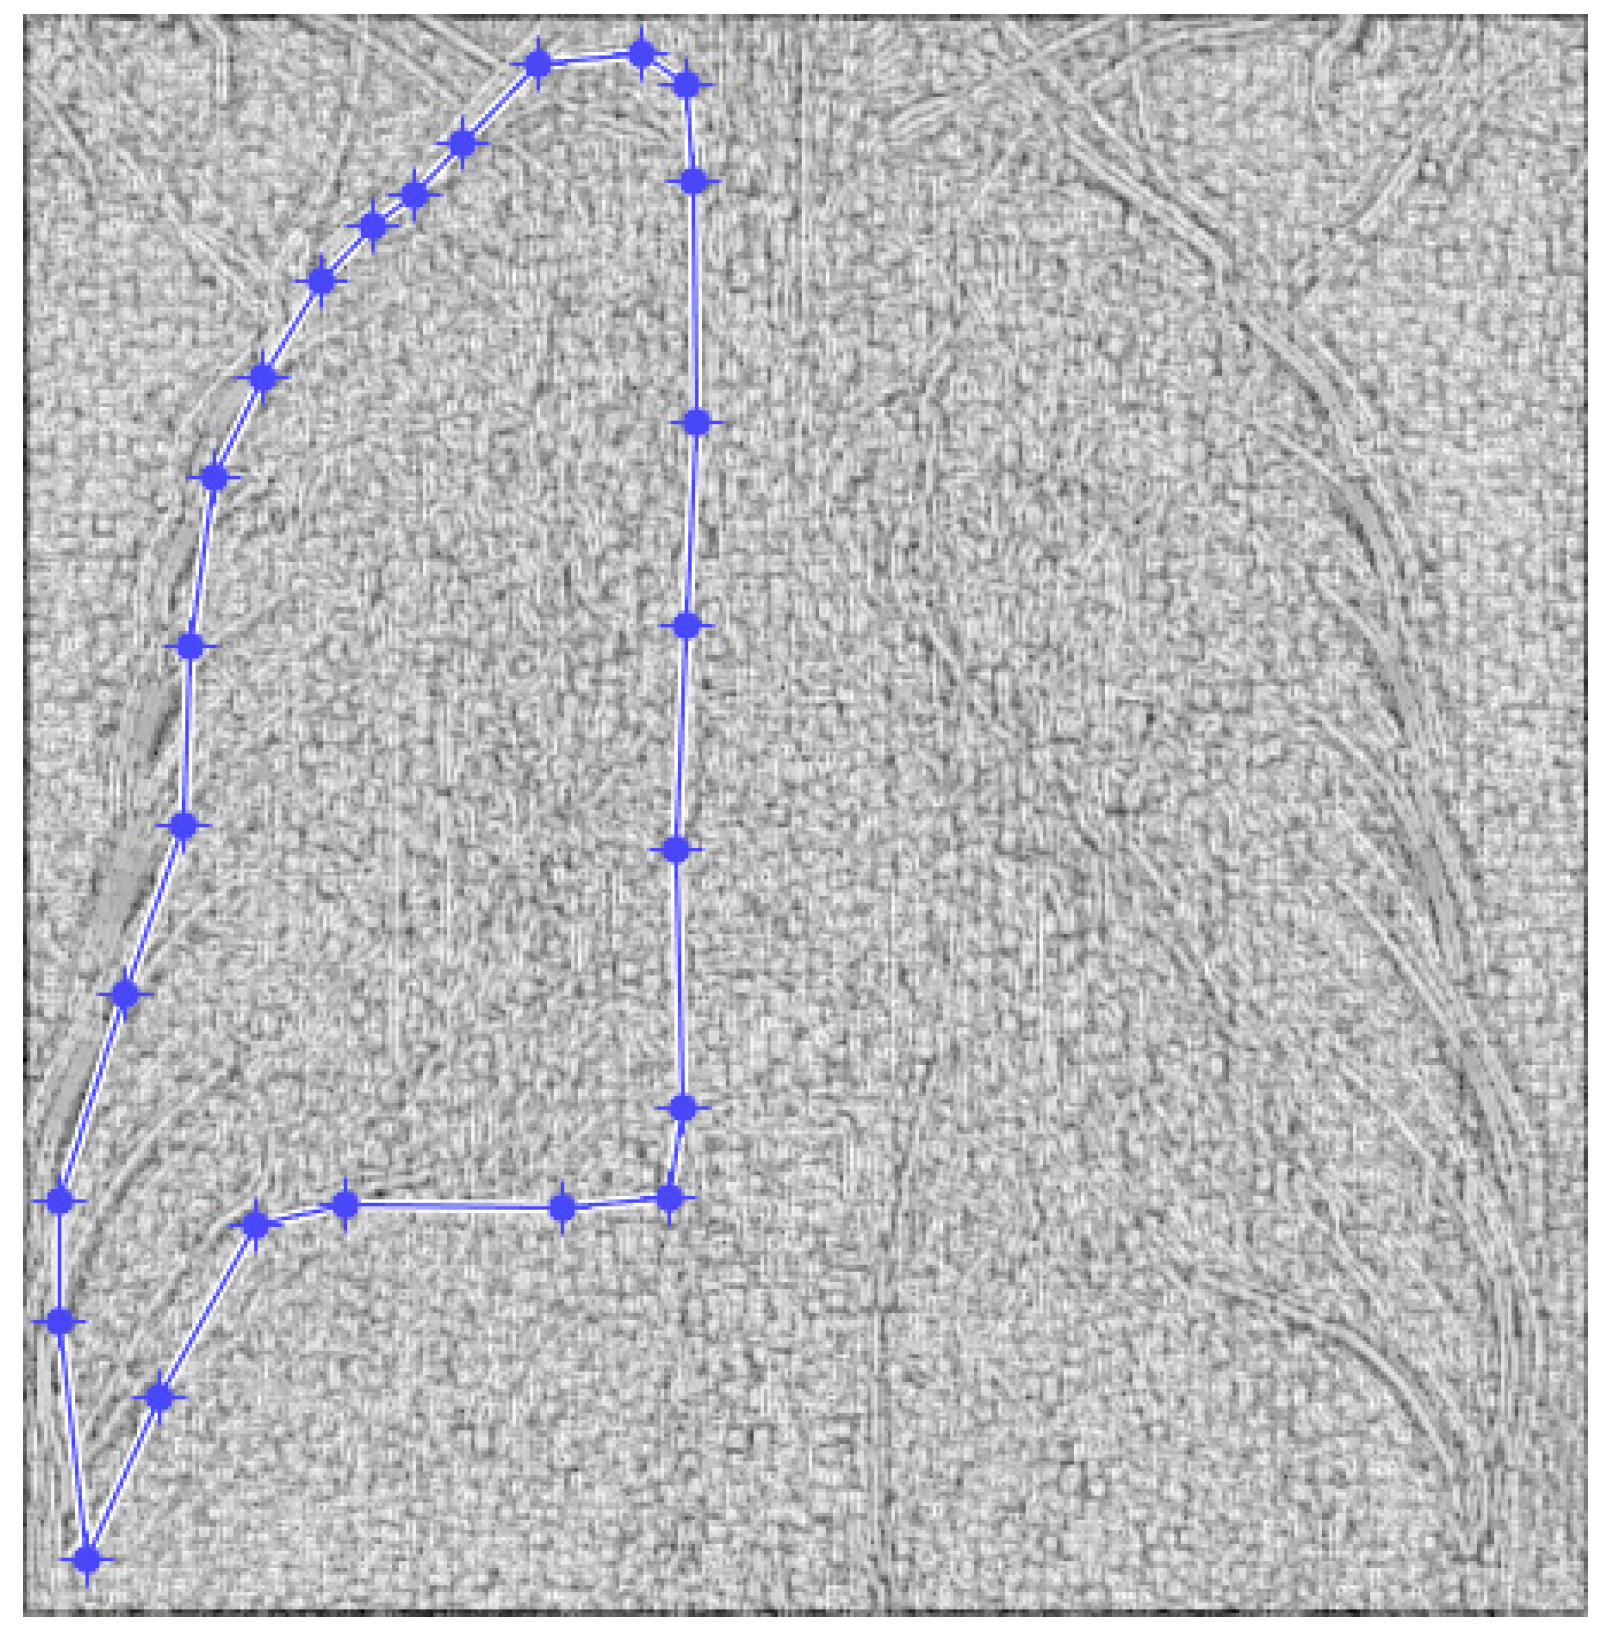

Figure 4. Defining the mask for the left lung of the first patient.

Fractalfract 07 00285 g004

Figure 5. Defining the mask for the right lung of the first patient.

Fractalfract 07 00285 g005

Figure 4 and Figure 5 present the defined masks for the left lung and right lung, framed in blue borders.

Table 1 shows the known fractal indicators, such as the fractal dimension of the CT image of the left lung, d1L = 1.8781 ± 0.3251, and the lacunarity, Λ = 0.0300; and the fractal dimension of the right lung, d1R = 1.8817 ± 0.3267, and the lacunarity, Λ = 0.0301.